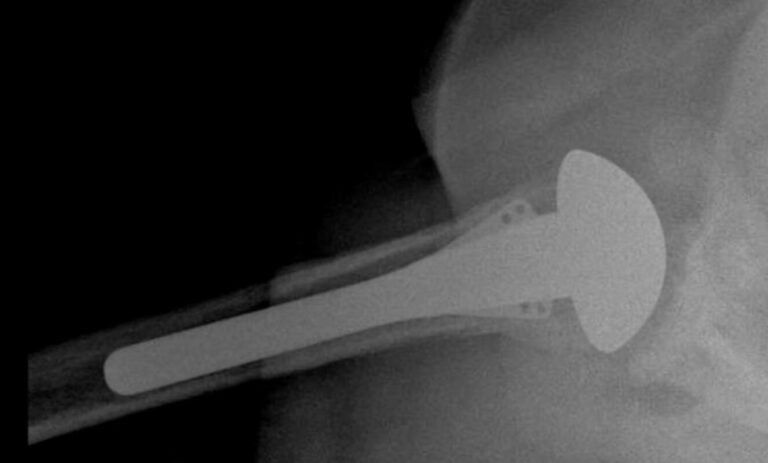

DJO/Enovis, Turon